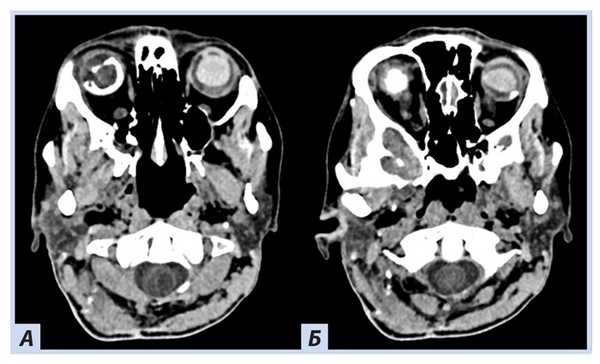

о ОЭЛМ → инфильтративные, деструктивные изменения каменистой части височной кости

(а) На рисунке аксиального среза у пациента с ФГЛ определяется опухоль эндолимфатического мешка — литическое гиперваскулярное объемное образование, имеющее геморрагический компонент. Образование залегает между ВСП и сигмовидным синусом. Обратите внимание на тенденцию к фистулизации внутреннего уха.

(б) Бесконтрастная КТ, аксиальный срез: у женщины 51 года с известным ФГЛ и нейросенсорной тугоухостью определяется классический признак данного заболевания — гиперденсная V-образная гемаоррагическая отслоение сетчатки, обусловленная ГМБЛ сетчатки («ангиома»).

(а) КТ височной кости: у той же пациентки определяется литическое поражение В задних отделов каменистой части левой височной кости инфильтративного характера. Обратите внимание на фиксированные костные «спикулы» внутри образования. Локализация и внешние признаки характерны для опухоли эндолимфатического мешка (ОЭЛМ).

(б) MPT, Т1 -ВИ, аксиальный срез: у той же пациентки определяется, что образование имеет смешанный изо - и гиперинтенсивный сигнал по сравнению с окружающей мозговой тканью. (а) МРТ, Т2-ВИ, аксиальный срез: у той же пациентки определяется гетерогенный гиперинтенсивный сигнал от образования. Обратите внимание на гипоинтенсивный сигнал от левого стекловидного тела по сравнению с нормальным правым глазным яблоком.

(б) МРТ, постконтрастное Т1-ВИ, режим подавления сигнала от жира: у той же пациентки определяется интенсивное, но гетерогенное контрастирование образования. Кровоизлияние в сетчатку гиперинтенсивно на Т1-ВИ.